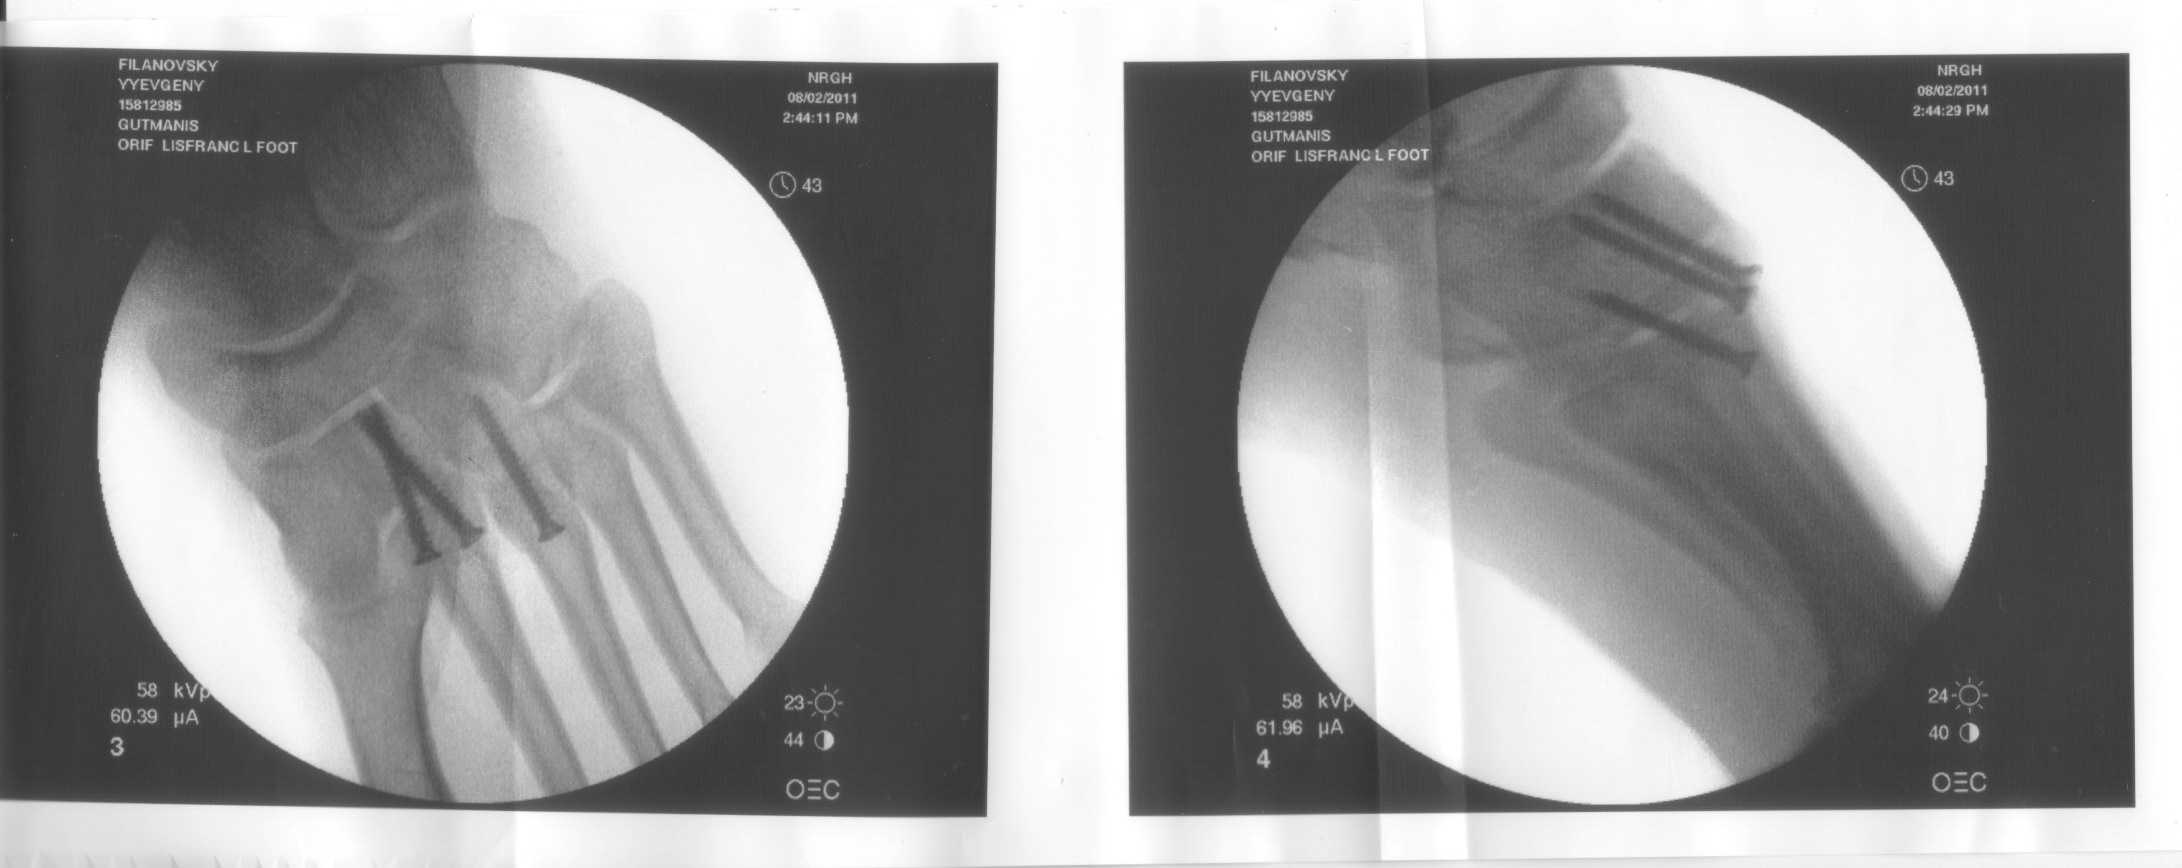

Two weeks post blowing my foot apart... A lisfranc fracture/dislocation of my midfoot. Basically a seperation of your forefoot from your midfoot along the metatarsals. Bunch of small fractures involved but it's mostly a ligamentous thing. Very bad injury. Blows apart the arch in your foot. Commonly associated with WS because of the footstraps and associated leverage which can occur in the area. This is one of a few things that can happen if you go backwards while board and rig go forwards and your feet are buried deep in the straps. Mine was very atypical... feet actually popped out of the straps after a jump, holding boom got thrown forward over nose of board after it hit the water, and my foot hit the rail of the board as I passed over it at high speed.

Very long recovery from this injury. Hopefully see you all at the beach next year, but I'm done for the season.